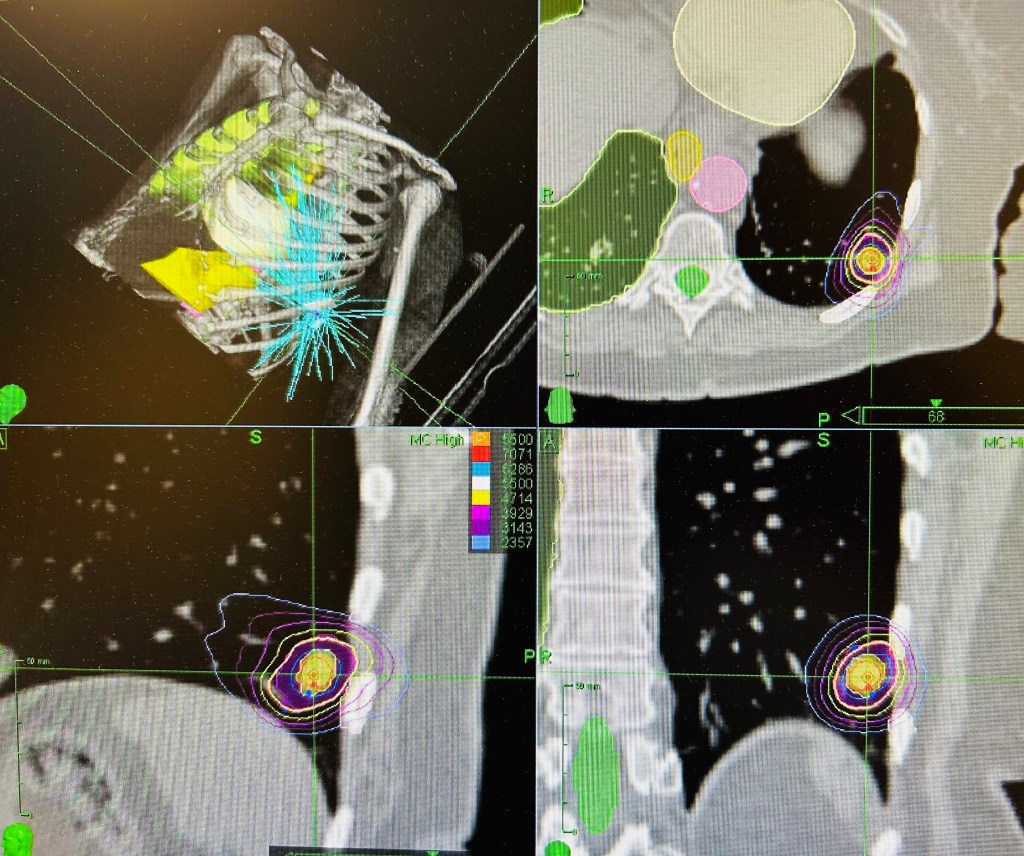

There was a good discussion of central vs peripheral tumors. While peripheral tumors can be safely treated in 1-3 high dose sessions, tumors within 2cm of the central lung structures should be treated in 5 sessions. The SUNSET trial recently gives us an 8 session treatment for “ultracentral” tumors touching the central lung structures. Importantly, respecting the normal tissue tolerance took priority over tumor dose.